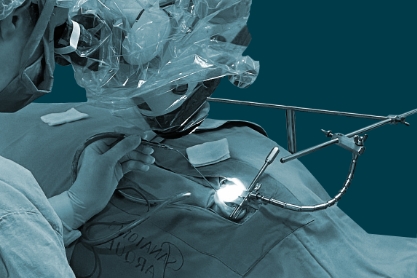

Cirugías

Cuando los audífonos son insuficientes, un implante coclear puede ser la solución adecuada para que vuelvas a vivir la experiencia de escuchar.